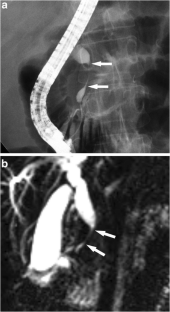

Fig. 1